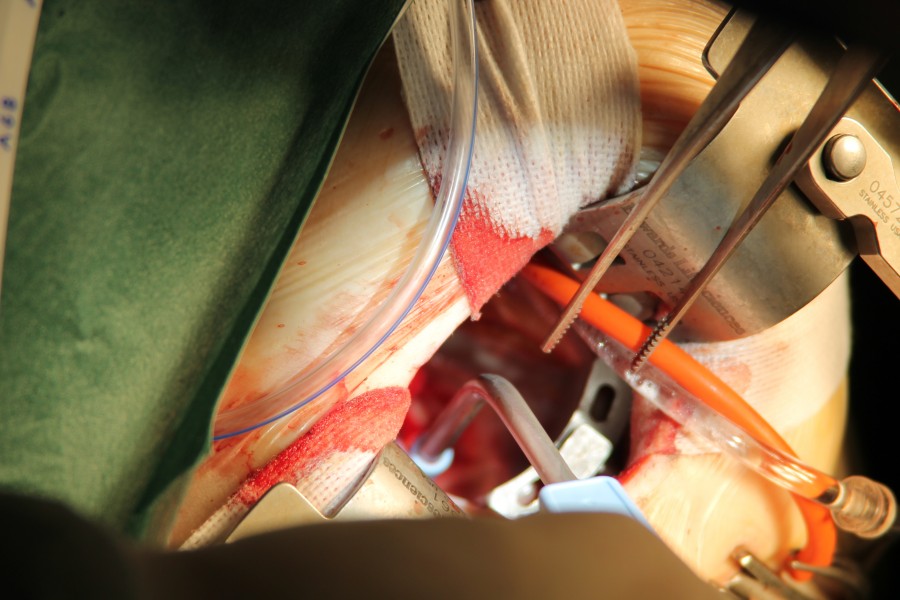

ANEURISMI

IMMAGINI DI ANEURISMI E INTERVENTI RELATIVI

VALVOLA MITRALE

INTERVENTO DI RIPARAZIONE-PLASICA- DI VALVOLA MITRALE PROLASSANTE CON ROTTURA